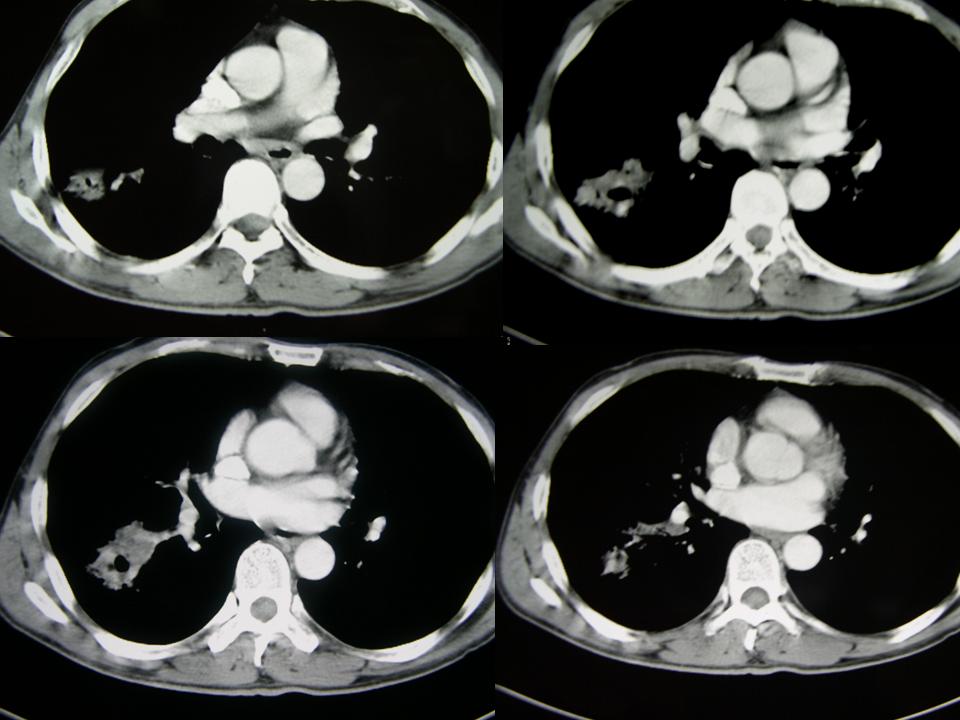

男性,65岁。主诉:干咳5年,加重月余。5年中多次发作,每次持续时间长短不一,静脉滴注缓解;近月余加重,用药效果差。晨起加重,痰少,无发热,无血丝

1、慢性支气管炎并肺气肿;

2、右下肺叶团片状影,见空泡征、分叶征、毛刺征及偏心性空洞,符合肺癌(腺癌可能性大)

考虑右肺下叶周围型肺癌(癌性空洞形成)并阻塞性肺炎。

病理结果:

谢楼主反馈病理结果(右肺下叶炎性病变伴小脓肿形成)。